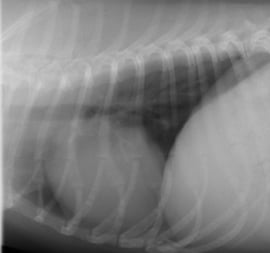

下記は以前のレントゲンシステムで撮影した画像と新しいレントゲンシステムで撮影した画像の比較です。

クリックして拡大していただくと、骨の鮮明さ、心臓の血管の見え方が新しいレントゲンシステムのほうが良くご理解いただけるかと思います。

新しいレントゲンシステムで撮影した画像